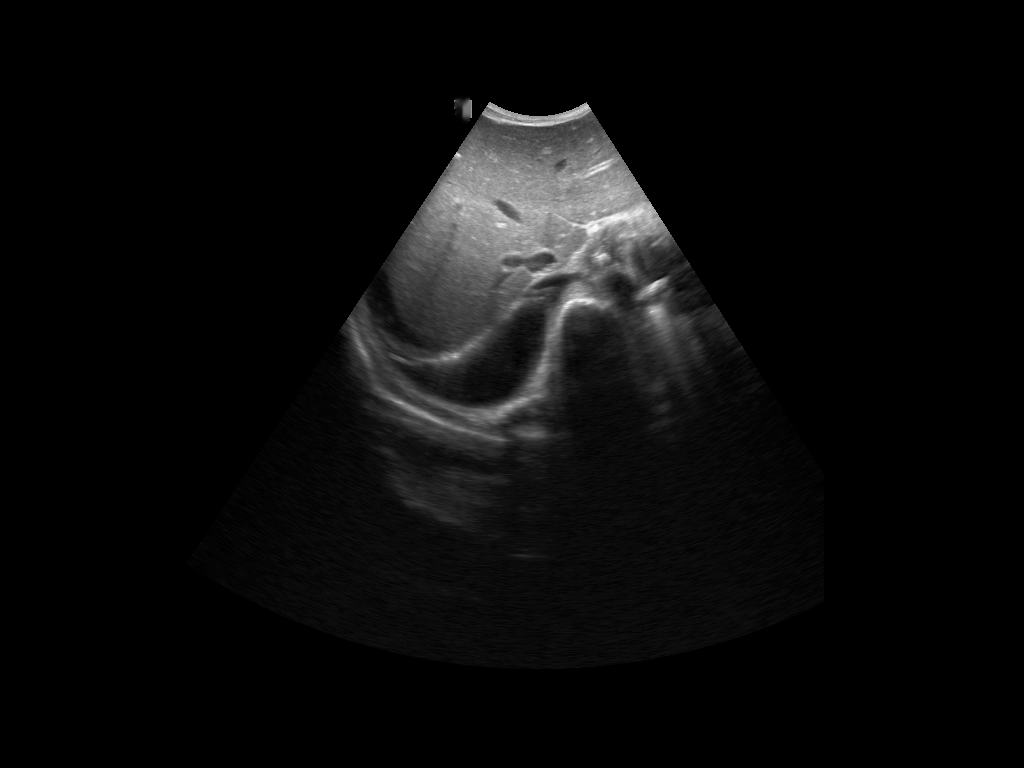

A total of 143 images were acquired from 59 patients. The images were obtained at the left and right PLAPS (PosteroLateral Alveolar and/or Pleural Syndrome) and subcostal views [4] with linear array and curved array (abdominal) ultrasound probes. The data were split according to the use of these probes into two datasets of 51 and 92 images, respectively for linear array and curved array. We denote these datasets as Dataset A (linear array) and Dataset B (curved array). All images were annotated at the time of acquisition to measure the extent of the effusion. These annotations consisted of small crosses at the top and bottom of the deepest area of effusion. See Figure 1 (left column) for example images.

Before being used for training and evaluating the models, each image was automatically cropped using a rectangular/cone mask to remove non-imaging content. Next, we applied an inpainting text algorithm using keras-ocr followed by template matching and edge detection algorithms from opencv to remove the annotations that were added to the images to measure the effusion. Examples of the outputs of this preprocessing are shown in Figure 1 (centre column).

All images in both datasets were manually segmented using the ITK-SNAP software [14] (www.itksnap.org) by a trained observer. Examples of ground truth segmentations are shown in Figure 1 (right column). These segmentations acted as ground truths for training and evaluating the proposed models. Additionally, a second trained observer performed independent segmentations of subsets of 10 random images each from the two datasets. These were used to compute an estimate of inter-observer variability in the manual segmentation process.

Rows 1-2: Dataset A. Rows 3-4: Dataset B.